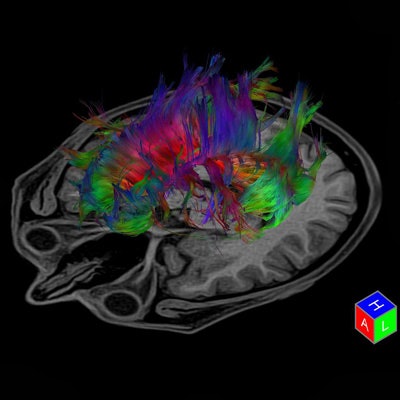

DTI provides qualitative and quantitative information about the microarchitecture of white matter. It can reveal information about the brain microstructure that may not be detected in conventional MR sequences of infants and children with brain malformations. With its ability to better categorize various brain malformations that may look similar on conventional MR imaging but may be caused by different pathomechanisms, DTI may allow transcending MRI from basic anatomic imaging toward function and embryology-based imaging. Conventional MRI is excellent in depicting the big functional centers, the nuclei of the brain. But it does not show how different parts of the brain are connected to each other or if there is an aberrant connection. DTI with fiber tracking does.

"Conventional anatomic MR imaging shows only the tip of the iceberg of microstructural brain malformations. DTI can be quite easily performed in any patient and provide a wealth of information. It is a matter of having the patience, perseverance, and a good knowledge of brain anatomy and function to 'connect the dots' and extract correct and relevant information out of a completed three-dimension tractography reconstruction," he explained.

While powerful postprocessing software programs may identify hundreds or thousands of white-matter tracts within a sampled brain, too many reconstructed fibers can obscure the relevant, aberrant, maldeveloped, or missing white-matter tracts, he added.

Many brain malformations are suspected from prenatal ultrasound data. DTI enables a quantitative analysis, and a structural analysis can be created through postprocessing and reconstructing the course of fiber tracts. As an example, if a neonate is not adequately moving his or her arms and/or legs, the cortical spinal tract can be reconstructed, specifically the fibers responsible for connecting the motor cortex and extremities. Huisman pointed out that it is necessary to know the clinical history of the patient to be able to pinpoint precisely what fiber tracts need to be reconstructed.

"If I am told that the child is not moving extremities, corticospinal fiber needs to be reconstructed; if there are memory problems, the limbic system; or if vision problems, the visual system," he stated.